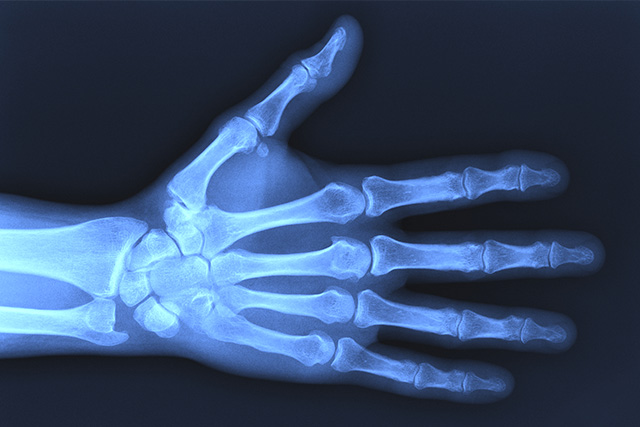

手・指の痛み